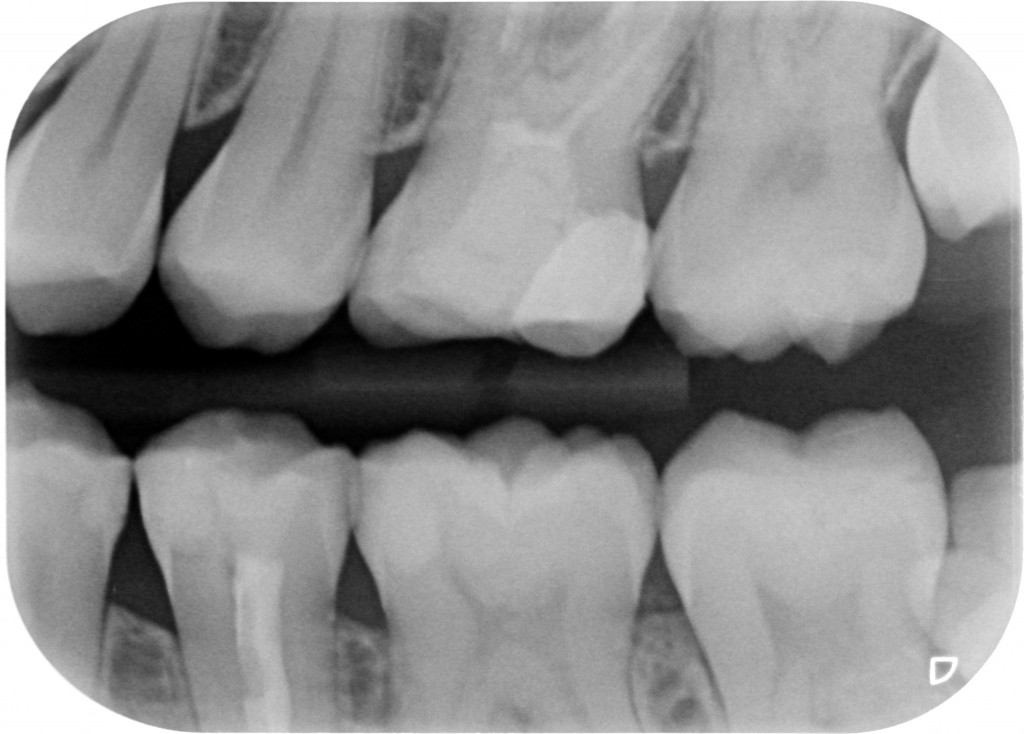

Comincio a fare una periapicale in alto a sinistra. Non centro bene la lastra e mi esce fuori questo.

Bah, potevo anche dedicare 10 secondi in più a centrare meglio…cmq quel che mi serviva lo vedo e cioè: NESSUNA CARIONA, SE NON UNA D1 SU 23, NESSUNA OTTURAZIONE ENORME A CONTATTO COL NERVO DI UN DENTE VIVO E UN DENTE DEVITALIZZATO CHE ANCHE SE CENTRATO MALE E PROBABILMENTE SENZA CANALE MV2 TROVATO NON MOSTRA GROSSE LESIONI PERIAPICALI.

Bah, potevo anche dedicare 10 secondi in più a centrare meglio…cmq quel che mi serviva lo vedo e cioè: NESSUNA CARIONA, SE NON UNA D1 SU 23, NESSUNA OTTURAZIONE ENORME A CONTATTO COL NERVO DI UN DENTE VIVO E UN DENTE DEVITALIZZATO CHE ANCHE SE CENTRATO MALE E PROBABILMENTE SENZA CANALE MV2 TROVATO NON MOSTRA GROSSE LESIONI PERIAPICALI.

Faccio allora una bite wing, stavolta centrata un po’ meglio a prendere anche la parte distale del 27 che mancava nella rx precedente…